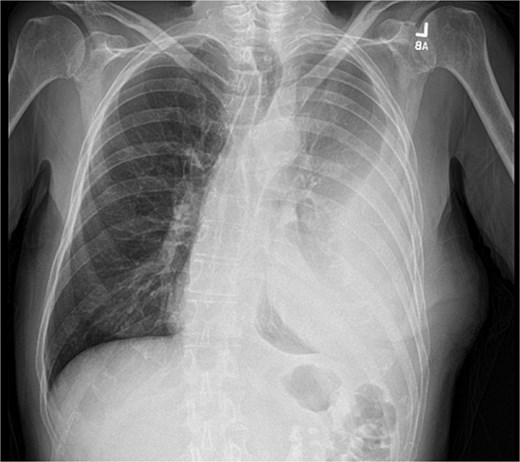

On presentation, chest radiography (Fig. 1) showed a large loculated left pleural effusion, and computed tomography (CT) scan (Fig. 2) confirmed the presence of the effusion with extension into the chest wall. The patient appeared ill with increased work of breathing. Physical exam revealed a large, fluctuant area with a solid component superior to the previous chest tube site, with no overlying skin changes. Blood work was significant for hyponatremia to 127 and a white blood cell count of 10.3 with no neutrophilic predominance. The patient was admitted, started on IV antibiotics, and dual antiplatelet therapy was held in preparation of surgical treatment of his EN. During this time, the fluctuant mass developed an opening, creating a pleurocutaneous fistula, and began to drain significant purulent fluid, which was sent for bacterial cultures.

Initial chest radiograph showing a large loculated left sided pleural effusion.